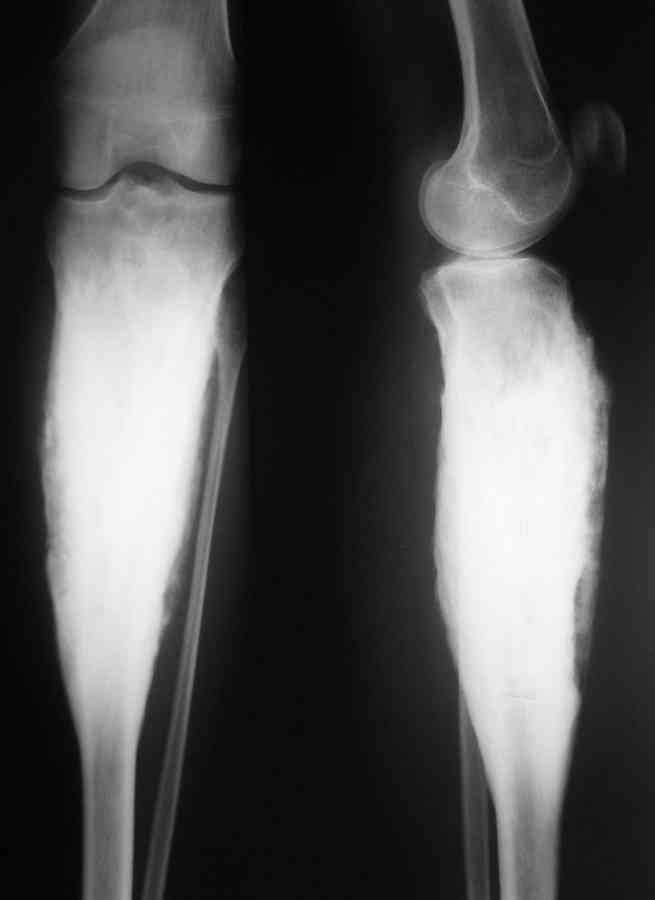

Господа, обратилась девушка 20 с небольшим лет.Больна с 2002 года. остеомиелит Гарре. Подтвержден гистологически.